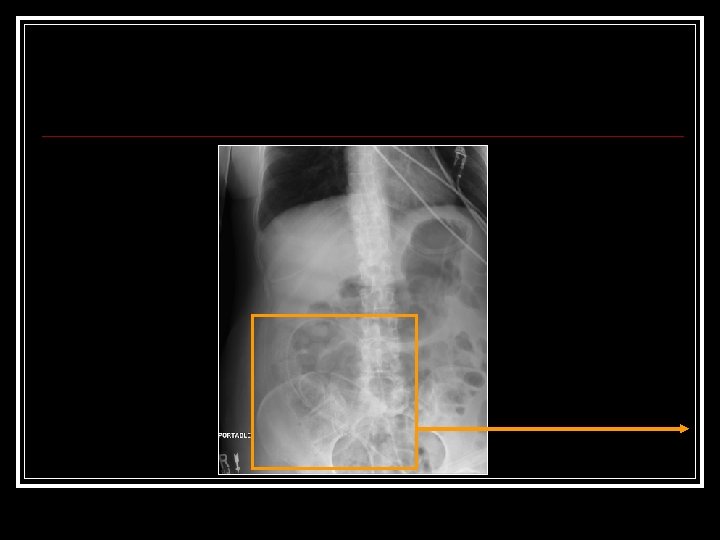

March 22 [cont’d] n n n Neuro. Surgery Consulted ? Shunt Malfxn Initial exam: Intub, withdrawing disconjugate gaze Drain off 20 cc via shunt reservoir Pt immediately awakes, begins reaching for ETT Cannot palpate distal shunt got AXR:

March 23 -26: Further 20 cc drained off [02: 00 am] n In a. m Cardiac cath: Normal Coronaries n Echo: Mild LV hypokinesis n Pt had shunt studies n went to OR third ventriculostomy n Pt does well. Discharged home n